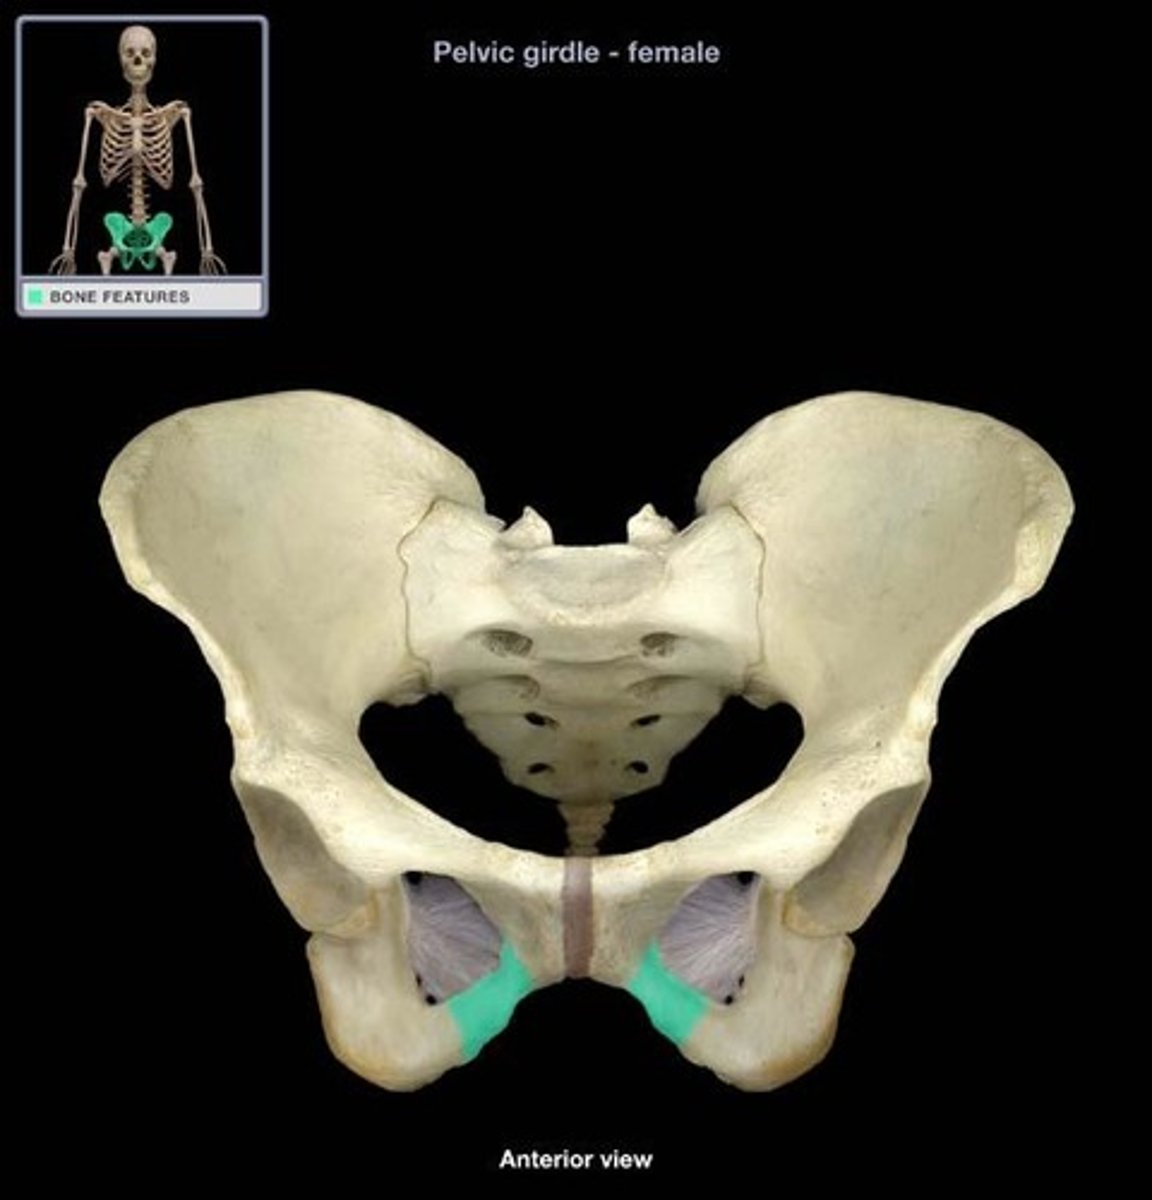

bony pelvis

2 coxal bones, sacrum, coccyx

pubic symphysis

cartilaginous joint at which two pubic bones fuse together

pelvic floor

The muscular base of the abdomen attached to the pelvis, supports pelvic organs, influence urination, defecation, sexual function

levator ani muscles

puborectalis, pubococcygeus, iliococcygeus

hiatuses in pelvic floor

urethral canal, rectal canal, vaginal canal

middle opening in the pelvic floor that allows passage of the fetus during birth